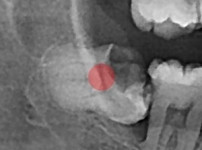

부분 매복 사랑니

조회

747

작성일

25-12-29